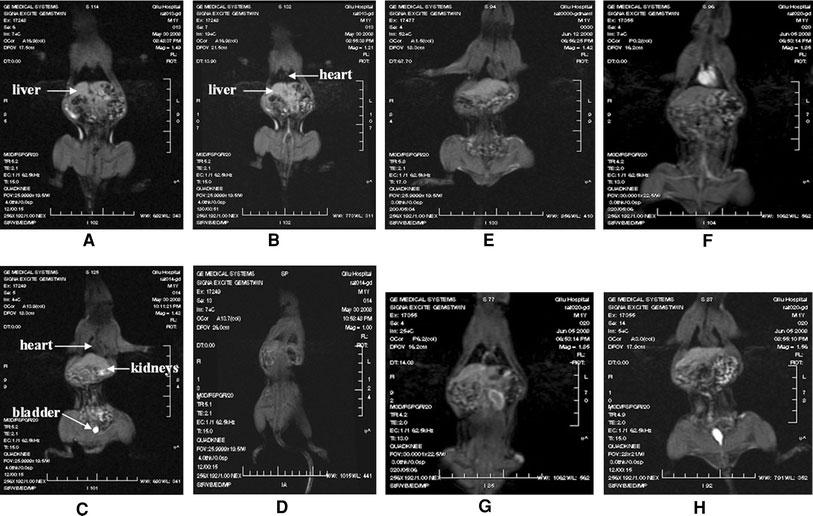

Accurate diagnosis in early stage is vital for the treatment of Hepatocellular carcinoma. The aim of this study was to investigate the potential of poly lactic acid-polyethylene glycol/gadolinium-diethylenetriamine-pentaacetic acid (PLA-PEG/Gd-DTPA) nanocomplexes using as biocompatible molecular magnetic resonance imaging (MRI) contrast agent. The PLA-PEG/Gd-DTPA nanocomplexes were obtained using self-assembly nanotechnology by incubation of PLA-PEG nanoparticles and the commercial contrast agent, Gd-DTPA. The physicochemical properties of nanocomplexes were measured by atomic force microscopy and photon correlation spectroscopy. The T(1)-weighted MR images of the nanocomplexes were obtained in a 3.0 T clinical MR imager. The stability study was carried out in human plasma and the distribution in vivo was investigated in rats. The mean size of the PLA-PEG/Gd-DTPA nanocomplexes was 187.9 +/- 2.30 nm, and the polydispersity index was 0.108, and the zeta potential was -12.36 +/- 3.58 mV. The results of MRI test confirmed that the PLA-PEG/Gd-DTPA nanocomplexes possessed the ability of MRI, and the direct correlation between the MRI imaging intensities and the nano-complex concentrations was observed (r = 0.987). The signal intensity was still stable within 2 h after incubation of the nanocomplexes in human plasma. The nanocomplexes gave much better image contrast effects and longer stagnation time than that of commercial contrast agent in rat liver. A dose of 0.04 mmol of gadolinium per kilogram of body weight was sufficient to increase the MRI imaging intensities in rat livers by five-fold compared with the commercial Gd-DTPA. PLA-PEG/Gd-DTPA nanocomplexes could be prepared easily with small particle sizes. The nanocomplexes had high plasma stability, better image contrast effect, and liver targeting property. These results indicated that the PLA-PEG/Gd-DTPA nanocomplexes might be potential as molecular targeted imaging contrast agent.